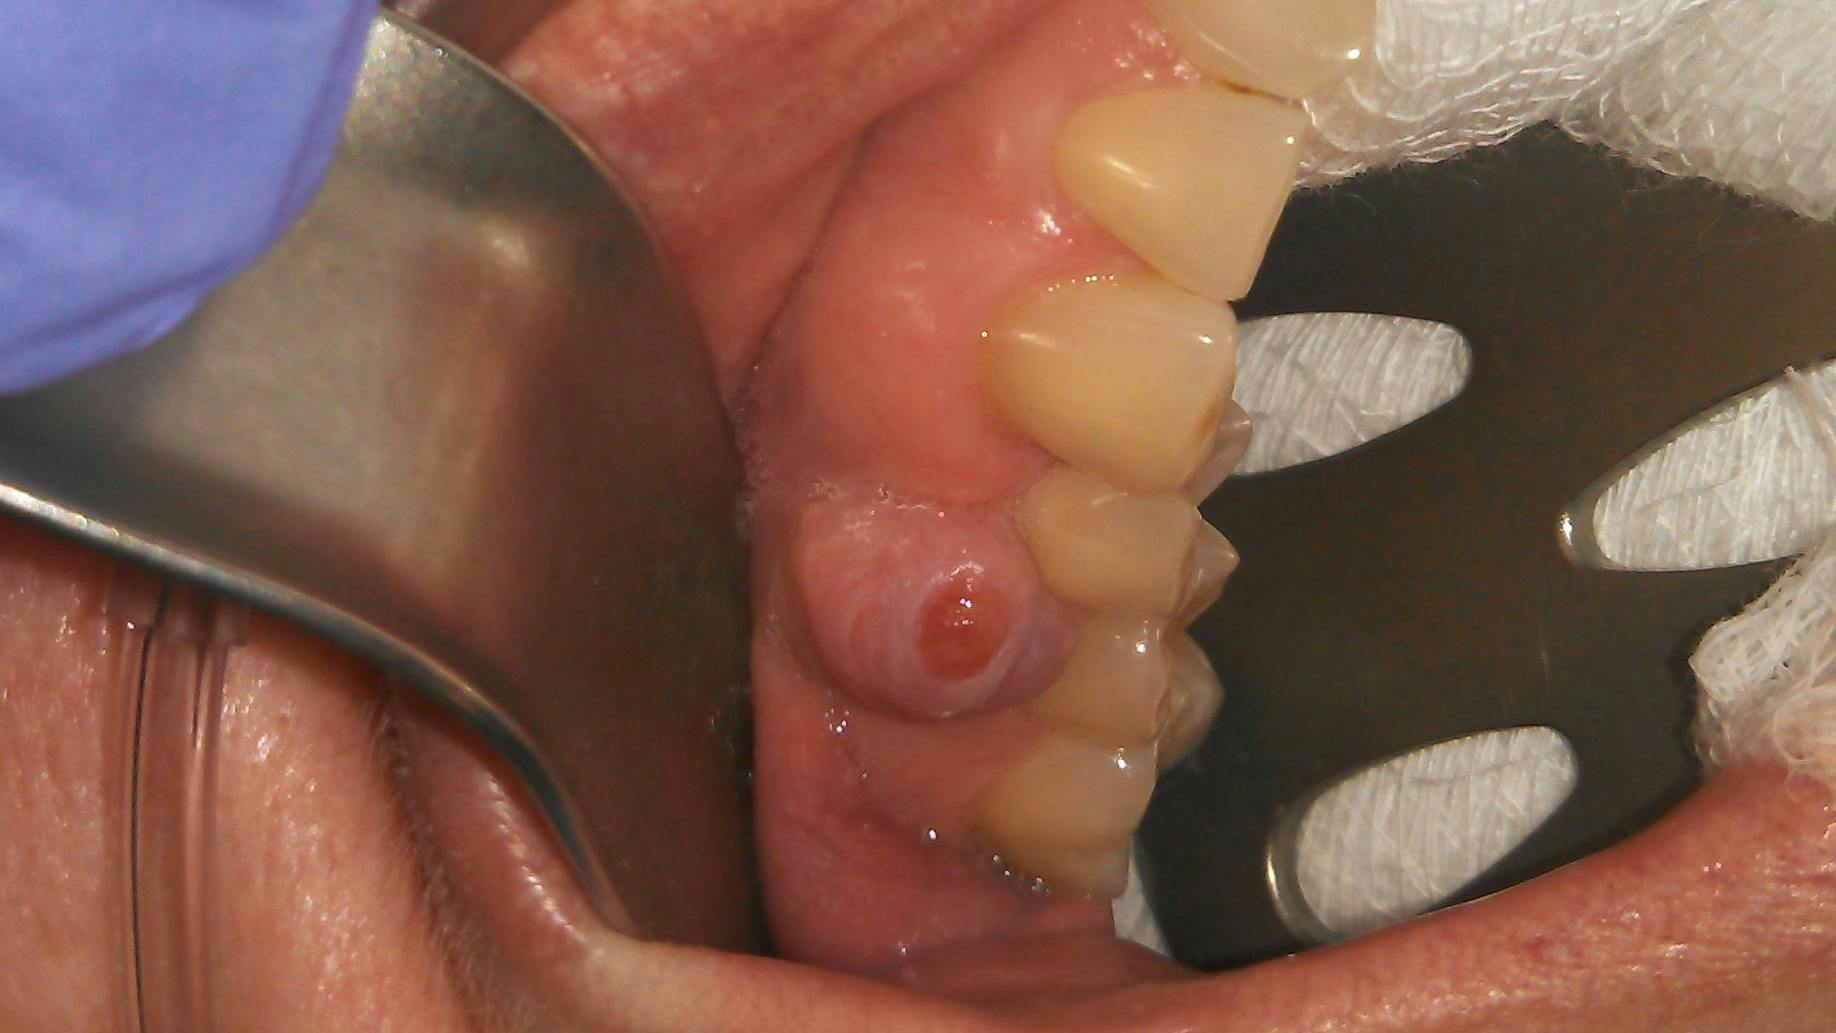

A 50-year-old female presented for a new-patient exam upon the recommendation of her general practitioner. Her chief complaint: “My doctor said that I have an infection on one of my top right teeth.” She pointed to a raised tissue mass between teeth nos. 4 and 5.

Clinical assessment revealed a 6 mm pink, raised, firm mass of osseous tissue measuring 12x12 mm. It was not tender to palpation and did not bleed easily when manipulated (figures 1 and 2). Radiographic assessment was within normal limits (figure 3).

In this particular case, the patient was referred to an oral surgeon for an assessment and biopsy. The lesion was removed and sent to pathology with a definitive diagnosis of peripheral ossifying fibroma (figures 4–6). The gingival defect created by the removal of the fibroma was allowed to heal by secondary intention and will likely undergo a free gingival graft later to reconstruct the attached gingival margin. The patient managed well without complications.